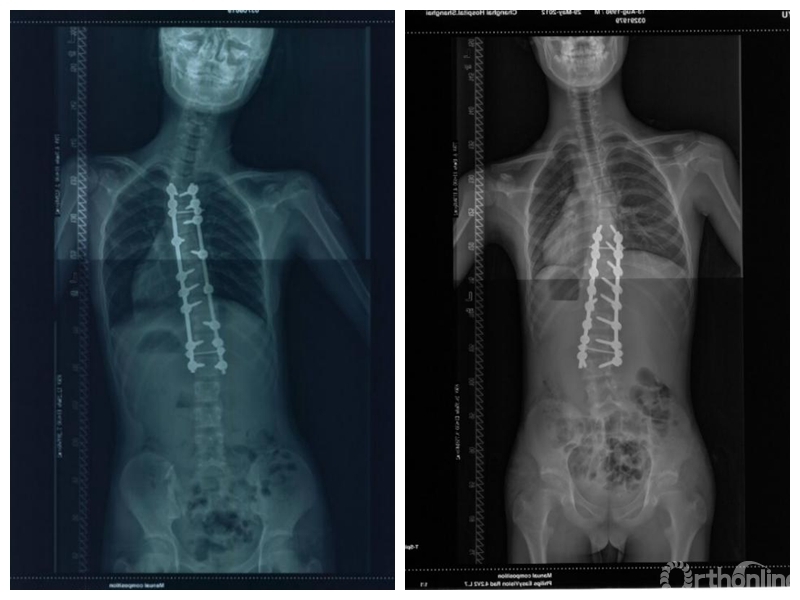

青少年特发性脊柱侧凸(adolescent idiopathic scoliosis,AIS)是青少年最常见的脊柱畸形疾病,以冠状位侧凸畸形、矢状位胸椎后凸减小和轴位椎体旋转为主要特点。随着对AIS研究的深入以及矫形技术的发展,AIS手术矫形效果得到了显著提高。然而在对AIS病人进行术后随访的过程中,脊柱外科医师发现了一类特殊的情况。这些病人在术后随访期间,融合节段下方出现了弯曲加重的表现,这就是近年来引起脊柱外科医师重视的问题——脊柱侧凸矫形术后远端附加现象(adding-on phenomenon)。

Wang等人[1]于2011年在Spine杂志上发表的文章中将远端附加现象定义为结构性主弯融合术后随访1年及以上时,主弯范围延长,最下固定椎(lowest instrumented vertebra,LIV)下方有更多椎体进入主弯,LIV以下第一个椎体偏离骶骨中垂线(center sacral vertical line,CSVL)5mm以上或LIV以下第一个椎间隙成角增加5°以上的现象。目前这一定义得到学界广泛的认可。远端附加现象多出现于行选择性胸弯融合的患者,主要是Lenke 1A型及Lenke 2A型AIS患者。其诊断标准为末次随访时,对比术后站立位脊柱全长正位片出现:

(1)主弯下端椎(lower end vertebra,LEV)向远端移动,主弯椎体数增加,LIV偏离CSVL 10mm以上;

(2)或是LIV以下第一个椎体偏离CSVL 5mm以上;

(3)或是LIV以下第1个椎间隙成角增加5°以上[1,2]。